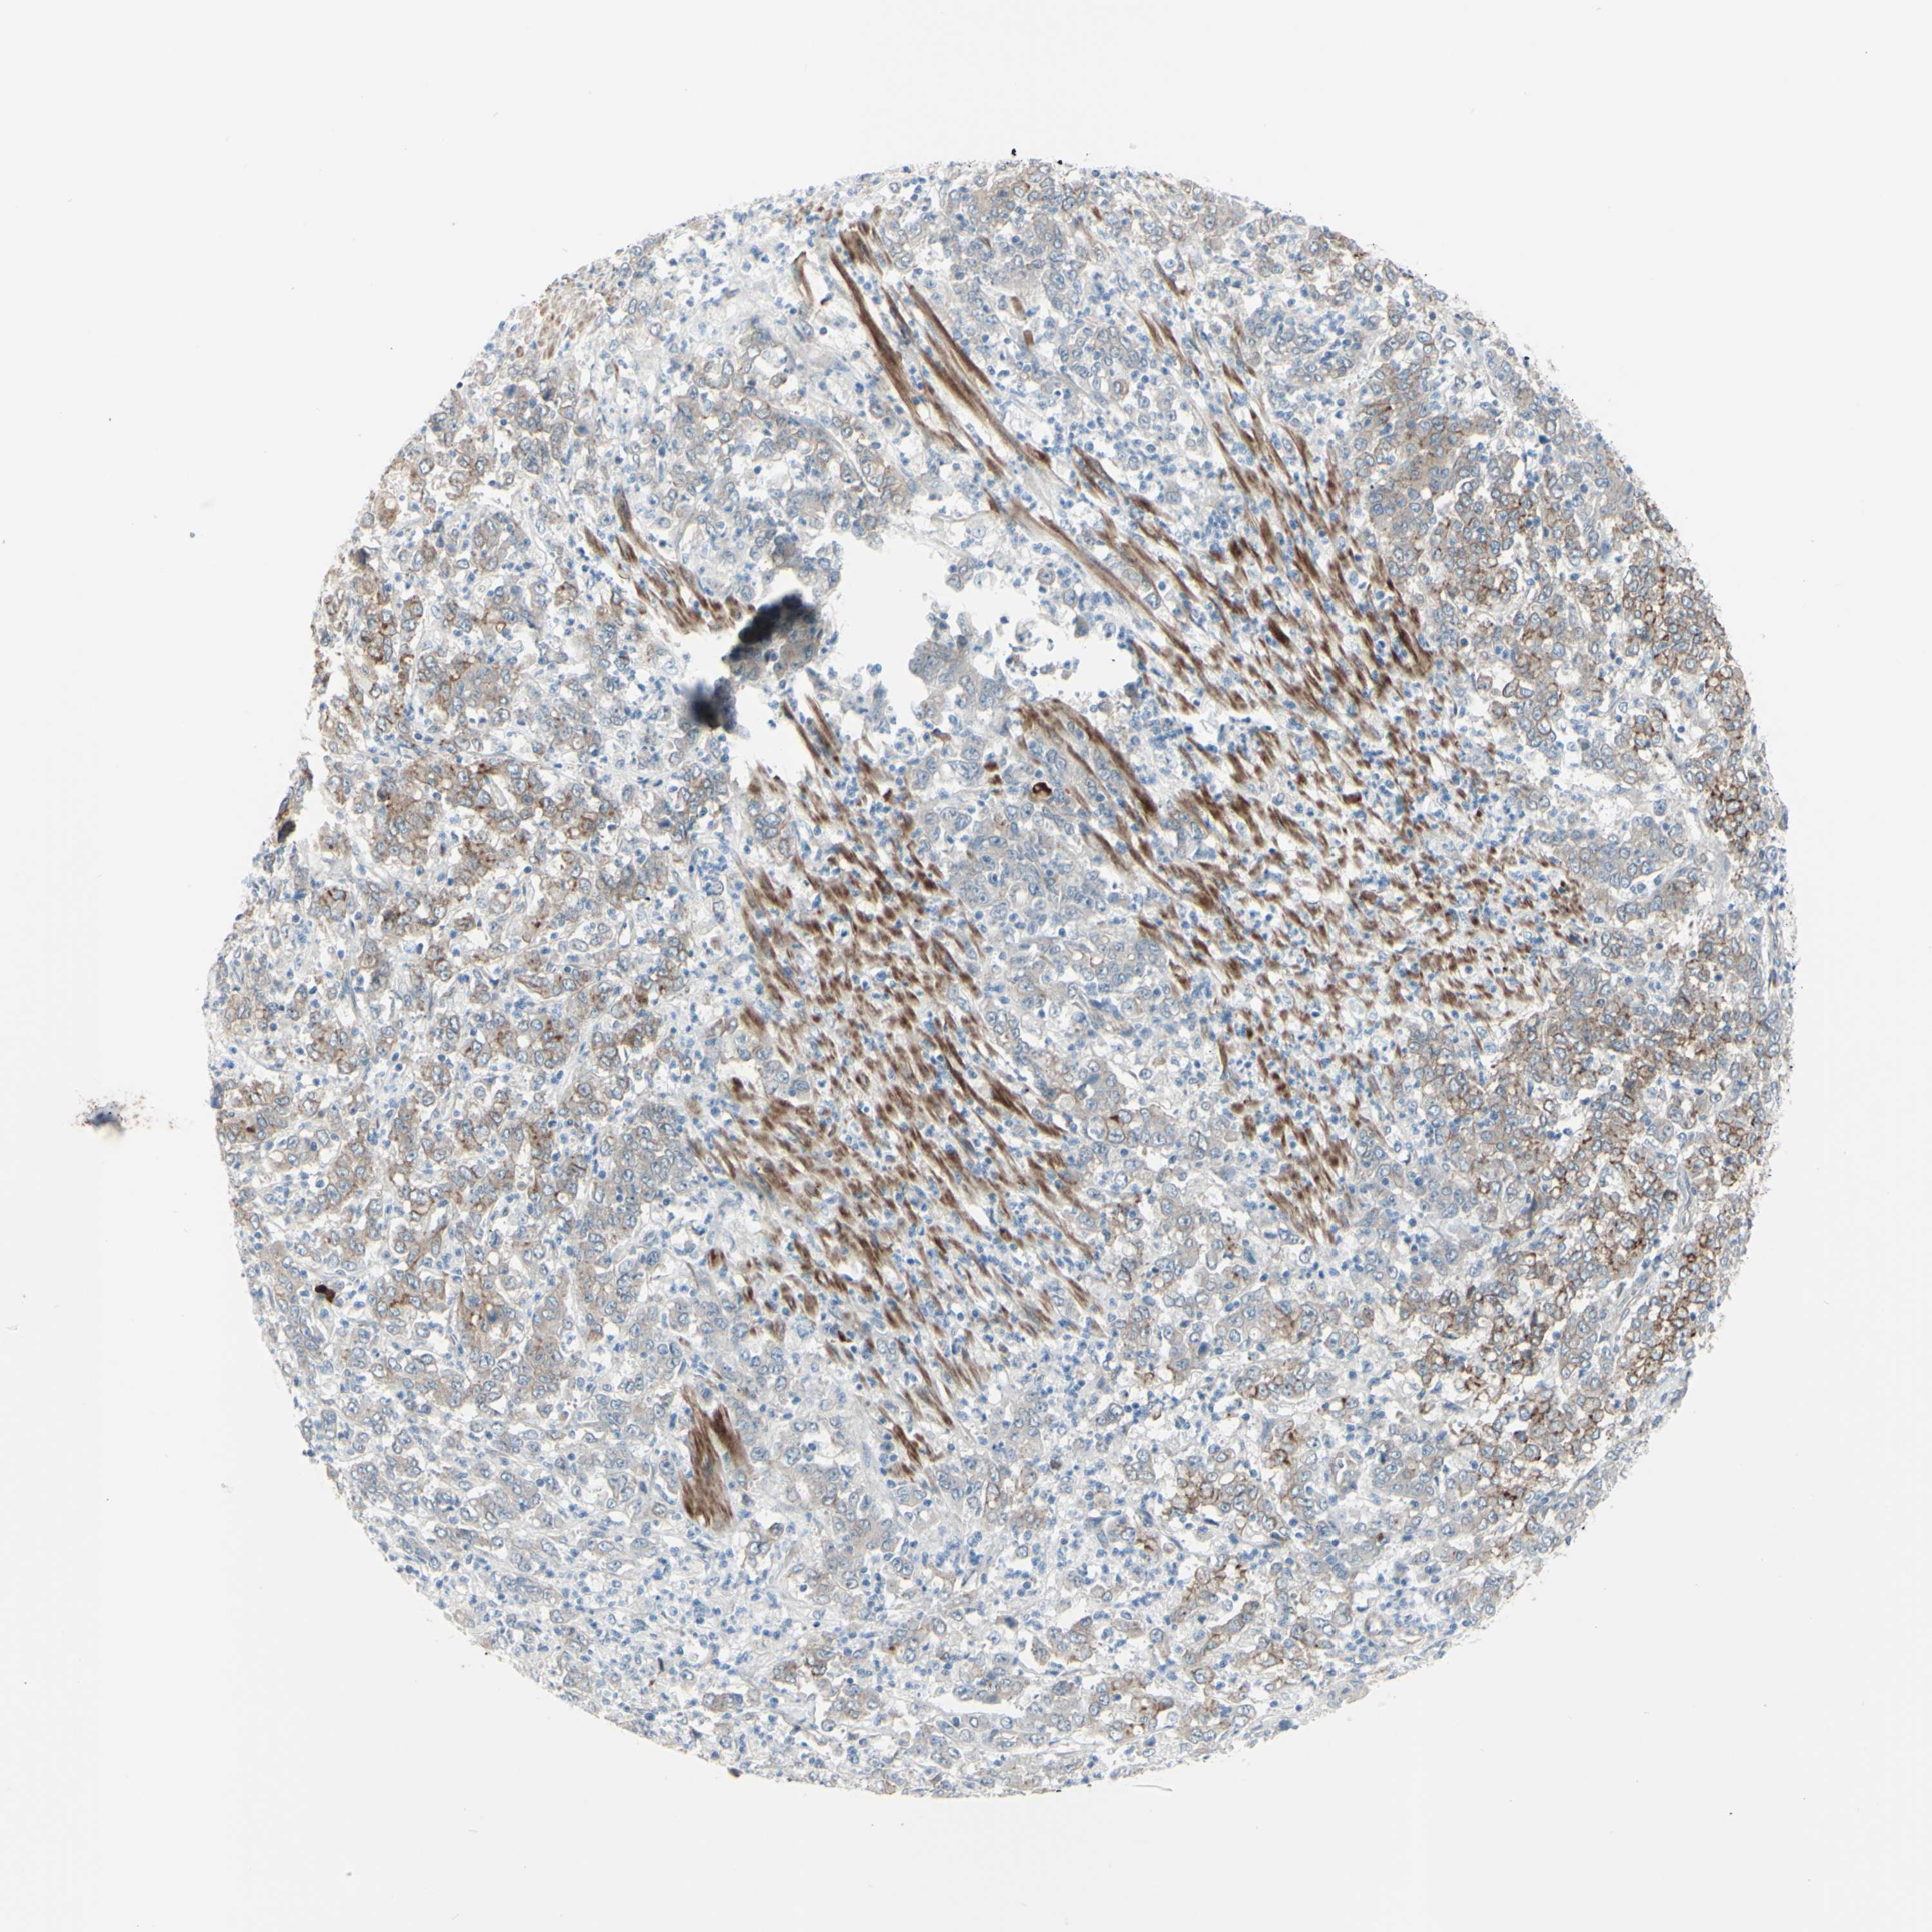

STOMACH CANCER - Protein expressioni

A mouse-over function shows sample information and annotation data. Click on an image to view it in a full screen mode. Samples can be filtered based on level of antibody staining by selecting one or several of the following categories: high, medium, low and not detected. The assay and annotation is described here.

Note that samples used for immunohistochemistry by the Human Protein Atlas do not correspond to samples in the TCGA dataset.

Antibody stainingi

Antibody staining in the annotated cell types in the current human tissue is reported as not detected, low, medium, or high, based on conventional immunohistochemistry profiling in selected tissues. This score is based on the combination of the staining intensity and fraction of stained cells.

Each image is clickable and will lead to virtual microscopy that enables deeper exploration of all samples and also displays staining intensity scores, fraction scores and subcellular localization as well as patient and tissue information for each sample.

Antibody HPA010537

Staining

High

Medium

Low

Not detected

Intensity

Strong

Moderate

Weak

Negative

Quantity

>75%

75%-25%

<25%

None

Location

Nuclear

Cytoplasmic/membranous

Cytoplasmic/membranous,nuclear

Adenocarcinoma, NOS

Adenocarcinoma, High grade